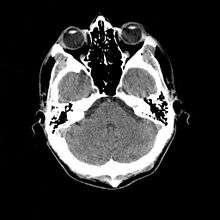

- Cranial computed tomography (CT, invented 1972) proved to be an excellent tool for diagnosing cerebral neoplasms in children, including those found in tuberous sclerosis.[46]

- MR was judged superior to CT imaging for both sensitivity and specificity. In a study of fifteen patients, it identified subependymal nodules projecting into the lateral ventricles in twelve patients, distortion of the normal cortical architecture in ten patients (corresponding to cortical tubers), dilated ventricles in five patients, and distinguished a known astrocytoma from benign subependymal nodules in one patient.[52]

- MR imaging was found to be capable of predicting the clinical severity of the disease (epilepsy and developmental delay). A study of 25 patients found a correlation with the number of cortical tubers identified. In contrast, CT was not a useful predictor, but was superior at identifying calcified lesions.[53]

- Cortical tubers found on MR imaging corresponded exactly to the location of persistent EEG foci, in a study of six children with TSC. In particular, frontal cortical tubers were associated with more intractable seizures.[55]